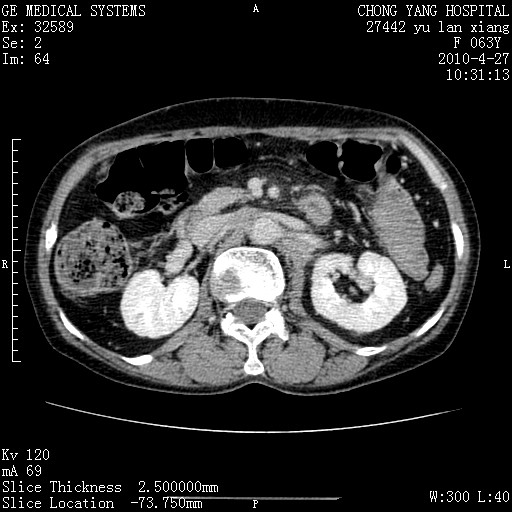

标题: CT26066:F63Y 上腹正中压痛半月,CA199:7400u/ml,MR示胰腺炎伴 [打印本页]

胰腺癌侵犯腹腔动脉干-分支、胃壁、左侧膈肌伴胰周及腹膜后淋巴结转移、胆囊切除术后。

胰腺癌侵犯腹腔动脉干-分支、胃壁、左侧膈肌伴胰周及腹膜后淋巴结转移、胆囊未显影。